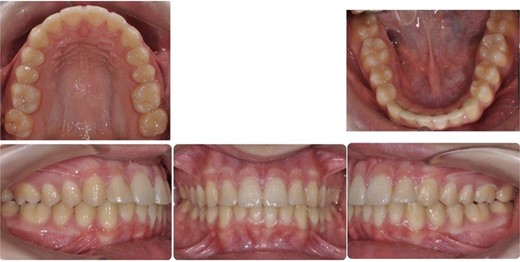

A 15-year-old male patient of Asian origin presented for orthodontic treatment with the chief complaint of crowding in his lower front teeth. Intra-oral clinical examination revealed severe crowding in the mandible, mild crowding in the maxilla, a bilateral class II canine relationship, retroclined upper incisors, impinging deep overbite and overjet of 5 mm (Fig. 1). His convex soft tissue profile and smile analysis revealed a decreased incisal show (Fig. 2).

Pretreatment intra-oral photos showing severe mandibular crowding.